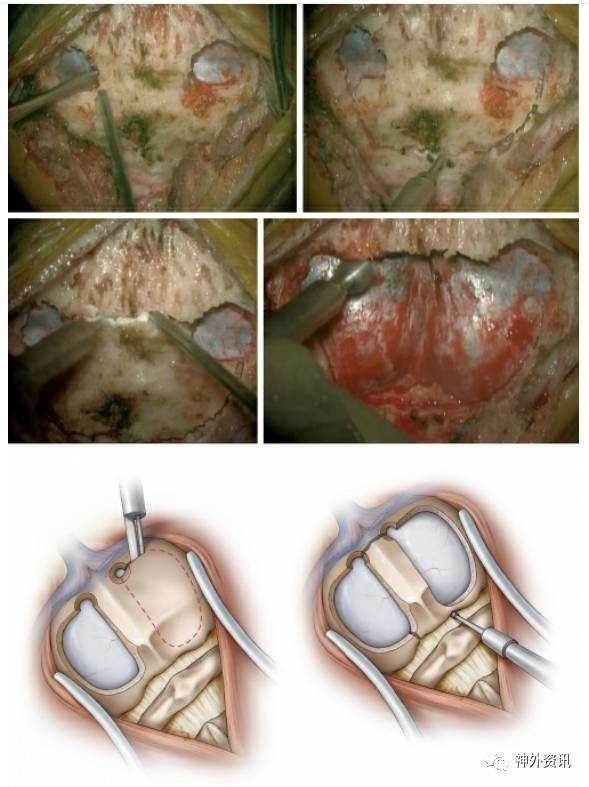

图8. 作者采取在横窦上方的枕骨钻两个孔,将硬脑膜和横窦、窦汇的壁从枕骨内壁分离。然后借助踏板在硬脑膜上方用开颅器切割骨瓣。为了保护静脉窦,在其上方进行最后切割时借助B1 bit而不用踏板。或者,在硬膜上方完成开颅术后用磨钻将静脉窦上方骨头逐层磨掉(上图)。

其它选择包括在中线两侧分别进行两个小的开颅术(左下图),然后再将中线的骨头切断(右下图)。咬骨钳可以将骨窗向侧方延伸到枕骨髁的位置(该图根据Tew,van Loveren和 Keller的图片重新绘制 )。

图9. 对于枕骨大孔区和上颈椎的损伤,为了更广泛的开放硬脑膜和充分暴露损伤区域,需要进行寰椎椎板切除术。通常沿着枕骨大孔移除骨瓣,可以提供一个更灵活的经膜髓帆入路到达第四脑室病变的通道。

Y型剪开硬脑膜,切口尽量向下延伸以便将硬脑膜瓣更好的向两侧移动。硬膜上方切口延伸到横窦下方。中线部位的病变,硬膜可以沿着中线切开;这种方法可以使术后硬脑膜缝合的更加严密(该图根据Tew,van Loveren和 Keller的图片重新绘制 )。

图10. 打开覆盖在小脑延髓池上的蛛网膜来释放脑脊液,从而减轻脑部受压。根据实际病变,用蛛网膜刀和纤维剪解剖中线的蛛网膜(左图)。经小脑蚓或膜髓帆入路更容易到达第四脑室病变(右图)(该图根据Tew,van Loveren和 Keller的图片重新绘制 )。